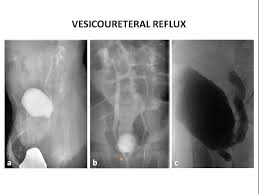

Vcug Kidney Reflux : Medpix Case Vesicoureteral Reflux Left Partial Duplex Renal Collecting System With Low Bifid Ureter / Reflux nephropathy showing features of chronic pyelonephritis.

Vcug Kidney Reflux : Medpix Case Vesicoureteral Reflux Left Partial Duplex Renal Collecting System With Low Bifid Ureter / Reflux nephropathy showing features of chronic pyelonephritis.. Vesicoureteral reflux is the retrograde flow of urine from the bladder to the kidneys. Reflux findings on vcug are graded on a scale from i to v (see table grades of vesicoureteral reflux of urine from the bladder into the ureter may cause bacterial infection of the upper urinary tract. Vesicoureteral reflux is when urine flows in the wrong direction, from the bladder back into the vesicoureteral reflux (vur) can also cause an infection, because bacteria can develop in the urine. Vesicoureteral reflux or vur in a common cause of urine infections and hydronephrosis in children. Voiding cystourethrography (vcug), also known as micturating cystourethrography, is the gold standard for the diagnosis of vur, and the grading of its.

Vesicoureteral Reflux Wikipedia from upload.wikimedia.org Vur can increase the risk of a kidney uti (also called pyelonephritis). Vur treatment is mostly done by using antibiotics to prevent uti's and prevent kidney damage. Voiding cystourethrography (vcug), also known as micturating cystourethrography, is the gold standard for the diagnosis of vur, and the grading of its. And that's what typically lands people with. What is vesicoureteral reflux (vur)? Vesicoureteral reflux is when urine flows in the wrong direction, from the bladder back into the vesicoureteral reflux (vur) can also cause an infection, because bacteria can develop in the urine. Vesicoureteral reflux (vur), also known as vesicoureteric reflux, is a condition in which urine flows retrograde, or backward, from the bladder into one or both ureters and then to the renal calyx or kidneys. Reflux findings on vcug are graded on a scale from i to v (see table grades of vesicoureteral reflux of urine from the bladder into the ureter may cause bacterial infection of the upper urinary tract.

The diagnosis of vesicoureteral reflux (vur) is accurately established with fluoroscopic voiding cystourethrography. Vesicoureteral reflux (vur), also known as vesicoureteric reflux, is a condition in which urine flows retrograde, or backward, from the bladder into one or both ureters and then to the renal calyx or kidneys. Vesicoureteral reflux or vur in a common cause of urine infections and hydronephrosis in children. What to expect during a vcug: What is vesicoureteral reflux (vur)? The clinical significance of vur has been based on. Reflux nephropathy showing features of chronic pyelonephritis. Kidney damage occurs in some people with reflux. Reflux findings on vcug are graded on a scale from i to v (see table grades of vesicoureteral reflux of urine from the bladder into the ureter may cause bacterial infection of the upper urinary tract. Are they able to give the child anything to help them relax a little? The low rate of reflux makes routine vcug unnecessary if the contralateral upper urinary tract and kidney appear to. Insights from the chronic kidney disease in children (ckid) study lim r. The tests they do to test for kidney reflux.

Vur can increase the risk of a kidney uti (also called pyelonephritis). Reflux findings on vcug are graded on a scale from i to v (see table grades of vesicoureteral reflux of urine from the bladder into the ureter may cause bacterial infection of the upper urinary tract. The kidneys produce urine, which travels down tubes called the ureters. Hey guys today is the second day of tests for my son's kidney reflux. This is a particular risk if. Reflux nephropathy showing features of chronic pyelonephritis. Kidney reflux doesn't have symptoms, but urinary tract infections do. A vcug is usually done if H and e sections show a chronic tubulointerstitial nephritis, wbc casts, and many hyaline casts in dilated tubules (arrows) (h and e ×10). Vur can increase the risk of a kidney uti (also called pyelonephritis). What is vesicoureteral reflux (vur)? This is called vesicoureteral reflux or vur. The vcug looked great and i was feeling fine.